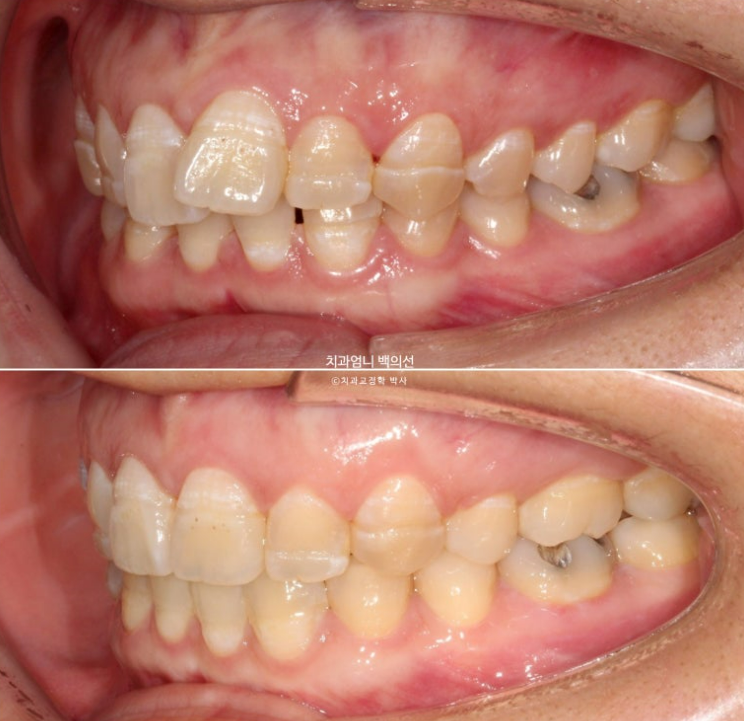

23년 10월 교정치료를 위해 찾아오신 30대 환자분입니다.

23.10

아래 앞니 사이에 벌어진 공간이 있고 위 앞니는 덧니가 있습니다.

앞니에 울퉁불퉁한 띠가 있는데 법랑질저형성증 입니다.

치아 건강에 문제가 되는 부분은 아니지만 오목한 부분에 음식이 잘 고입니다.

청결관리를 더 잘해줘야 합니다.

앞니가 튀어나와 돌출도 있습니다.

아래 앞니 4개 중 2개가 없습니다.

태어날때부터 없는 경우를 선천적 결손이라고 합니다.